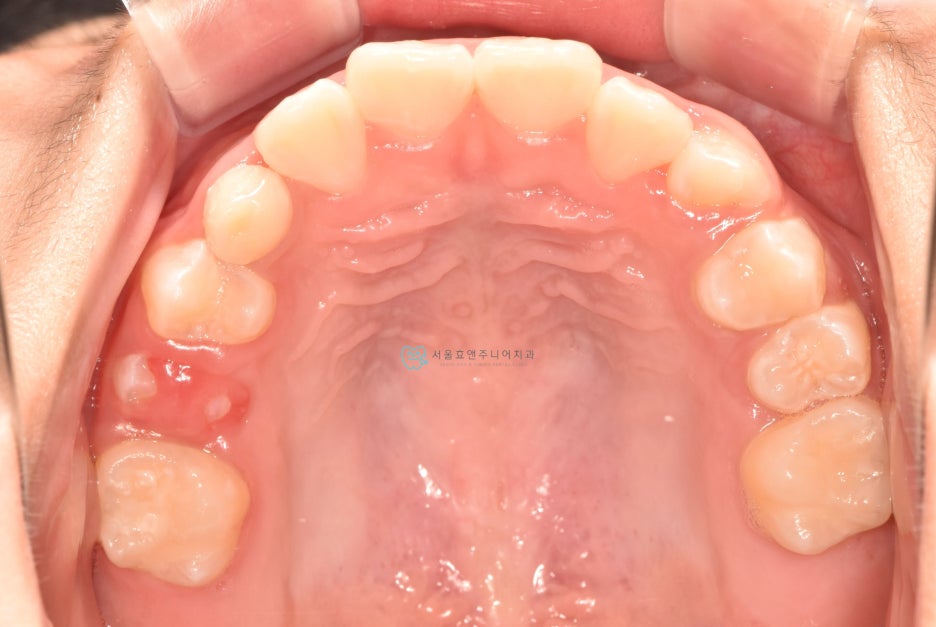

초진사진입니다

초진사진입니다. 11세 5개월 환아로, 반대교합을 보이고 있습니다. 반대교합으로 인해 치아가 부딪혀 치은퇴축(잇몸이 내려감)도 보이고 있네요.(화살표)